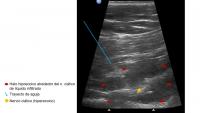

Se presenta el caso de un varón de 28 años remitido desde Traumatología por sospecha de meralgia parestésica. El paciente refiere que desde hace meses nota una especie de vibración en la cara anterolateral de...

Diagnóstico final: Meralgia parestésica